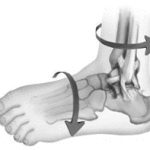

У голеностопного сустава блоковидная форма, он сгибается и разгибается в плоскости вокруг оси. Сустав состоит из сухожилий, связок, мышц, которые создают подвижность.

В частности, сустав создан из следующих анатомических элементов:

- пяточная таранно-малоберцовая связка,

- передняя таранно-малоберцовая связка,

- задняя таранно-малоберцовая связка.

Основным механизмом повреждения голеностопного сустава является ситуация, при которой стопа находится в фиксированном положении, а верхняя часть ноги в движении. При этом резко изменяется положение блока таранной кости. Она сильно упирается в передний край нижней части большеберцовой кости, в результате чего происходит его отламывание.

Травма голеностопного сустава может произойти в результате наружной ротации, отведении и приведении стопы, а также вертикальной компрессии. В клинической практике перелом голеностопного сустава происходит в результате сочетанного воздействия вышеперечисленных сил.